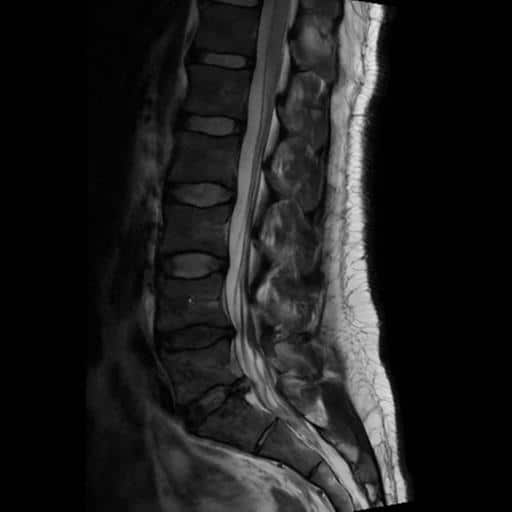

I got an MRI from a radiology clinic and confirmed that there was compression at the S1 nerve root. This at least ruled out more serious complications, but it also showed that we could really target that for recovery.

The injection was quick and easy. Just a couple of small pricks. First, the local anaesthetic, and then the injection. The radiologist looked at the imaging, and along with my symptoms, confirmed everything was consistent with an S1 nerve root inflammation. So that’s what he targeted.